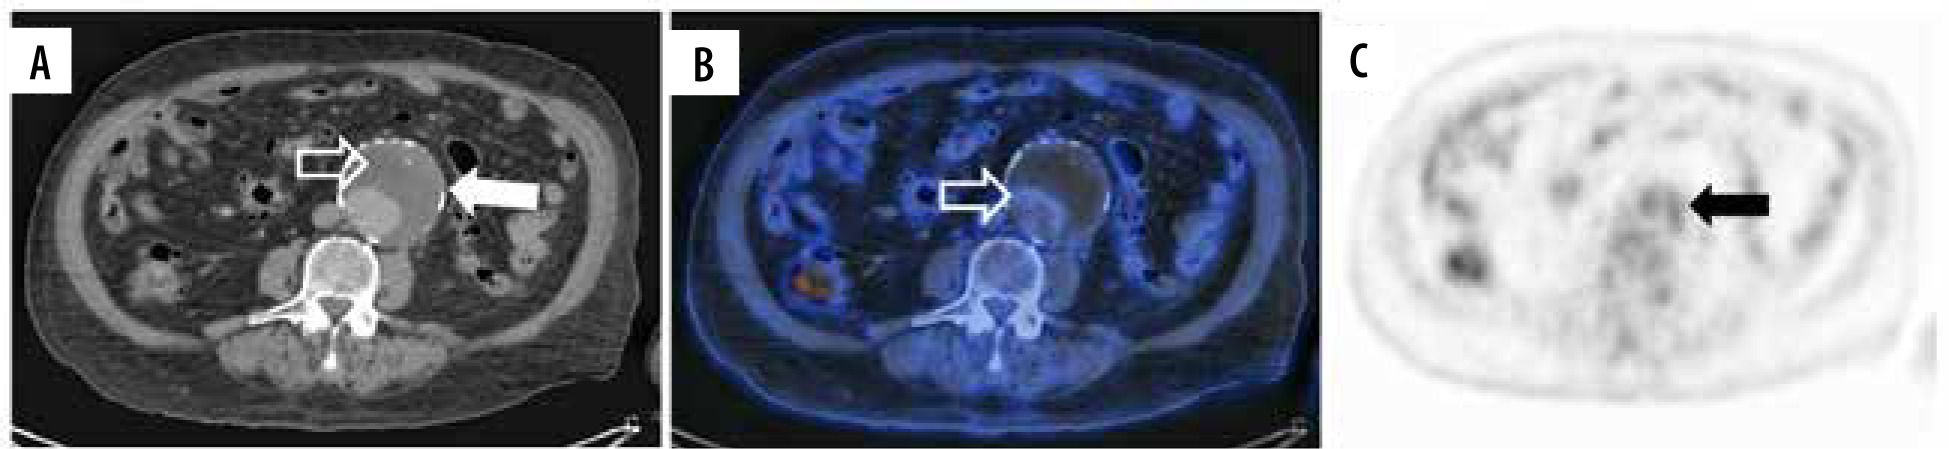

An aneurysm is a segmental vessel dilatation exceeding its average diameter by 50%, and it is the most common entity that affects the human aorta. The aortic aneurysm (AA) is in most cases asymptomatic until rupture, with a high mortality of 85 to 90%; thus, it is important for prompt diagnosis, evaluation, and treatment by a vascular surgery team [10]. In this process, several complex pathophysiological mechanisms are involved in the progression of AA, which are potential targets in molecular imaging such as inflammation, angiogenesis, proteolysis, and extracellular matrix remodeling [11,12]. In PET/CT, one of the most commonly used tracers is fluorine-18-fluorodeoxyglucose-6-phosphate (18F-FDG), which accumulates in sites of increased glycolysis such as inflammation [13] and cells with high metabolic activity such as cancer cells and macrophages. Recent literature correlates 18F-FDG uptake with vessel wall pathology (Figures 1A-C, 2A-C) and increased rates of rupture. An important limitation is the poor specificity in inflammatory states, but cells related to this process play crucial roles in AA pathogenesis [14].

Figure 1

18F-FDG PET/CT axial view of an abdominal aortic aneurysm (AAA) in a patient with a pancreatic neuroendocrine tumour (this patient refused treatment by the vascular surgery team in our institute). A) Simple CT of a 7.4 × 7.6 cm AAA (white arrow) with chronic intraluminal thrombus (hollow white arrow). B) Hybrid image showing an increased 18F-FDG uptake at the thrombus periphery (hollow white arrow) and the aortic lumen. C) PET scan increased 18F-FDG uptake at the thrombus periphery (black arrow)